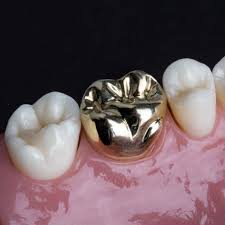

| 메탈 크라운 | 25~30만 원 |

| 골드 크라운 | 50~55만 원 |